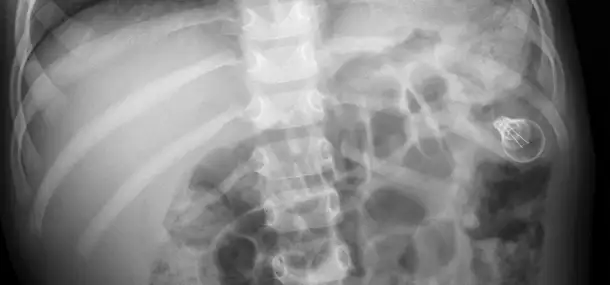

Another hazard is when children put small pieces of decorations into their mouths and accidentally swallow them. In fact, swallowed objects are the most common thing we are asked to help with when it comes to holiday hazards. They might sound surprising, but the list of things we have seen children swallow around the winter holidays includes:

If your child ever swallows an object (holiday or otherwise), it is best to try and bring a piece of that object or another similar object with you to the hospital so that we can compare it to what we see on your child’s medical images.